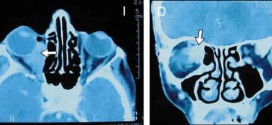

CARCINOMA EPIDERMOIDE DE OÍDO MEDIO

El carcinoma epidermoide de oído medio. Los carcinomas epidermoide de oído medio son raros 1-2/1000000/año. CAE/oído medio: 10/1. Tipo histológico más frecuente Ca epidermoide (70%), seguido del Ca basocelular. Durante los primeros años de vida de una persona, las células normales se dividen más rápidamente para permitir el crecimiento. El cuerpo está compuesto por billones de células vivas. Las células …